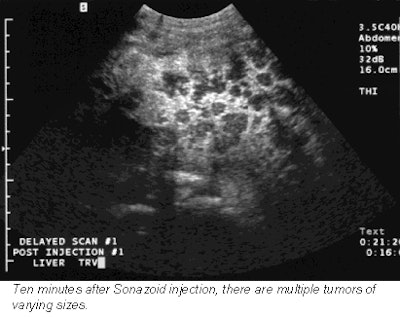

Next, each patient received an injection of Sonazoid, which was immediately followed by a pulse-inversion harmonic ultrasound scan that tracked the contrast in the bloodstream. A second scan 15 minutes later detects the contrast as it accumulates in liver cells. The contrast-enhanced scans boasted a 76% improvement in lesion conspicuity, a sensitivity improvement from 73% to 89%, and a jump in the number of confirmed metastases from 68 to 83.

![]() |

These promising results can be credited to Sonazoid’s long-lasting parenchymal phase, which is a measure of how long the bubbles remain in healthy liver cells before dissipating, said Dr. Laurence Needleman, an associate professor of radiology at Thomas Jefferson University in Philadelphia.